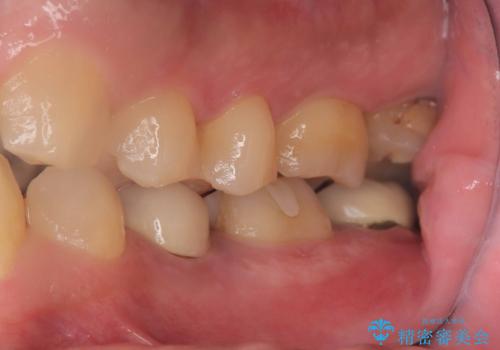

また、左下6番には形態が不自然で適合不良のセラミックインレーが装着されていたため、二次カリエスのリスクを考慮し、オールセラミッククラウンによる治療を行いました。

手術は1回で完了し、被せ物を装着するまでの治療期間も約3か月と、身体的・時間的な負担を抑えることができます。